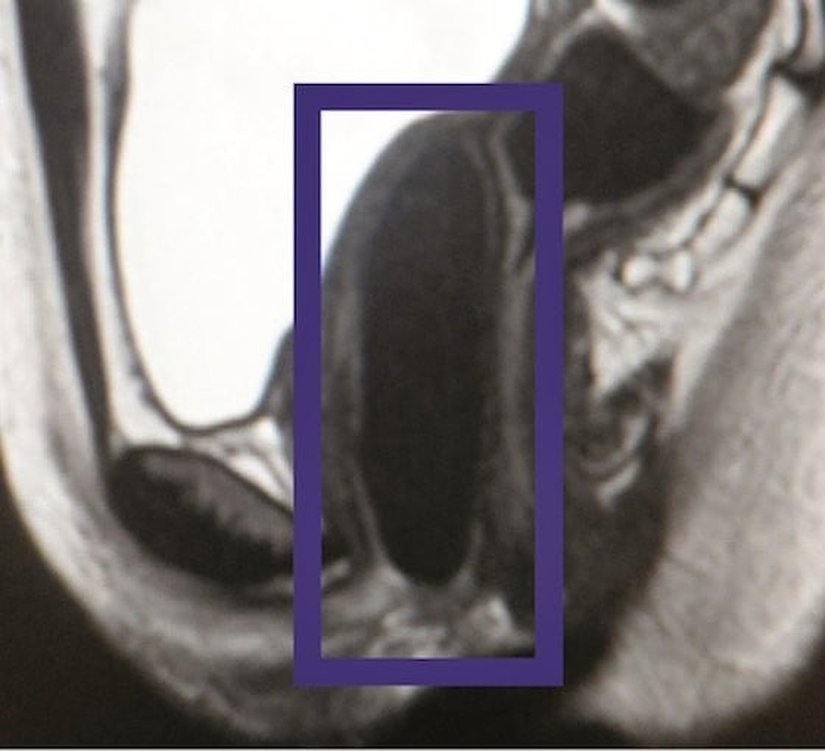

Bilim insanları 2005 ile 2008 yılları arasında Mexico City’den 4 hastaya, laboratuvar yapımı vajinanın nakledildiğini açıkladı. Doktorlara göre hastaların durumu, aradan 10 yıl geçmiş olmasına rağmen çok iyi. The Verge’nin raporuna göre nakil yapılmış olan hastalar Mayer-Rokitansky-Kuster-Hauser sendromu denilen ve nadir görülen bir genetik durumla doğdu. Bu önemli başarı 11 Nisan 2014’te The Lancet dergisinde yayımladı. Her 4.500 dişiden biri MRKH sendromu ile doğuyor. Bu kişilerin vajina ve rahimleri ya az gelişmiş oluyor ya da hiç var olmuyor.

13 – 18 yaşları arasında bulunan hastaların yaşı ameliyat için uygundu. Geleneksel olarak bu ameliyatlar acılı bir genişletme ve ameliyat süreçleri içermekteydi ve hastalar için travmatik olabiliyor ve genelde başarısız oluyordu. MRKH ile mücadele etmek için girişilen bir diğer denemede araştırmacılar her hastaya uygun vajinalar oluşturdu.

Operasyondan sonra, hastanın sinirleri ve damarları kademeli olarak büyüdü ve laboratuvar yapımı vajinanın içine entegre olmaya başladılar. Zamanla yapay kalıp tamamen kayboldu ve artık ona ihtiyaç kalmamıştı, geçen zaman içerisinde hücreler kendi kalıcı destek yapısını oluşturdu.